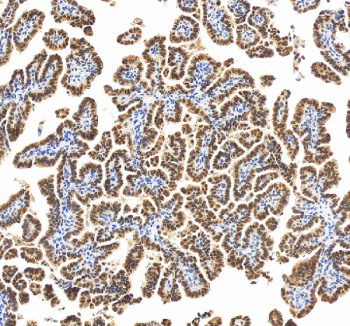

Immunohistochemical staining of RBM17 using anti-RBM17 antibody. RBM17 was detected in a paraffin-embedded section of human ovarian cancer tissue. Heat mediated antigen retrieval was performed in EDTA buffer (pH 8.0, epitope retrieval solution). The tissue section was blocked with 10% goat serum. The tissue section was then incubated with 2 ug/ml rabbit anti-RBM17 antibody overnight at 4oC. Peroxidase Conjugated Goat Anti-rabbit IgG was used as secondary antibody and incubated for 30 minutes at 37oC. The tissue section was developed using an HRP secondary and DAB substrate.